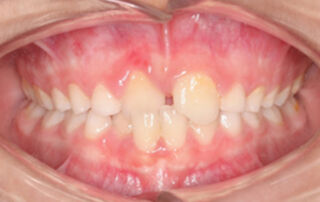

Caso clínico mordida cruzada anterior Quad Helix – 03

Paciente con 7 años de edad que presenta una mordida cruzada anterior dental (MCAD). En las imágenes intraorales iniciales observamos la mordida cruzada anterior del incisivo central izquierdo superior con el incisivo central izquierdo inferior. La paciente presentaba una clase I molar y canina, junto con una Clase I esquelética. [...]